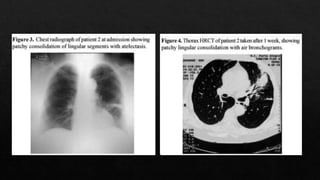

Es un Gramnegative, intracelular, obligado, que puede existir como un cuerpo reticular. Los organismos elementales, que son inactivos biologicamente y pueden sobrevivir en ambientes hostiles. La neumonía se desarrolla en 2 etapas: al inicio, los síntomas son similares a los de un resfriado (faringitis, laringitis, sinusitis), seguido de una neumonía moderada. La neumonía que dura entre 1 y 4 semanas es seguida por tos persistente que puede durar varias semanas.

Se estima quecausa 300,000 casos en EEUU cada año. Anti-C. pneumoniae anticuerpos son detectados en 50% de los individuos de 20 años. El porcentaje aumenta con la edad, teniendo un 70---80% en ancioanos. Tambien causa el 20% de las infecciones respiratorias bajas, y el 70% de los cuadros asintomaticos y leves, en los cuales se busca atencion medica. Un 3-10% de las neumonias adquiridas en la comunidad con causadas por este patogeno. En Latin America causa el 6% de estos cauadros, y es respondable del 20% de las einfecciones respiratorias altas Epidemiología